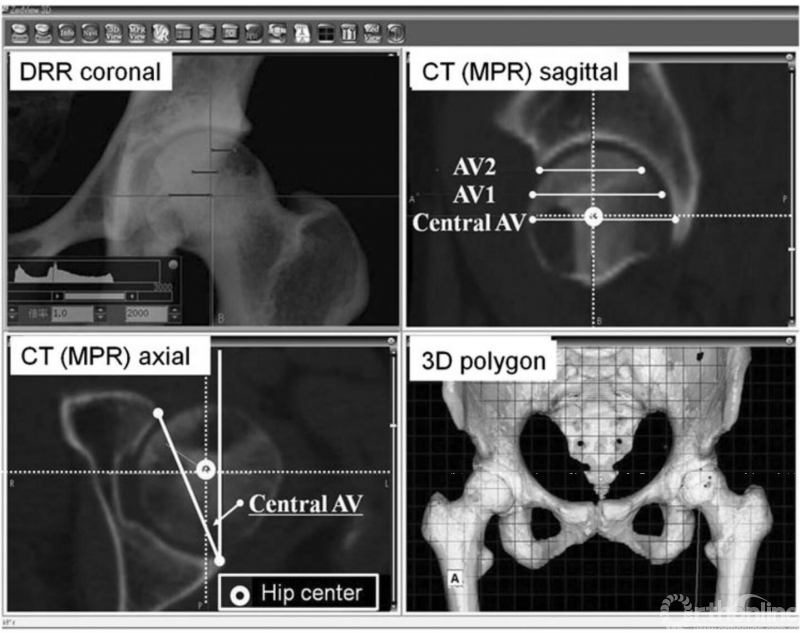

图3:Zed髋关节软件能重建3-D模型,并显示多平面重建(MPR)、数字X线片(DRR)影像,以替代普通平片。在3个垂直于TTP的横截面测量髋臼前倾角:中心前倾角((AV), AV1, AV2),使用DRR,在TPP代表的冠状面上测量p/a比值。